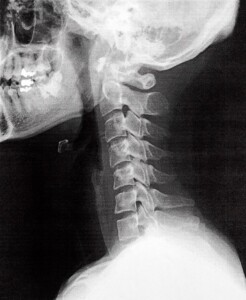

1. 頸椎症(けいついしょう)

加齢や姿勢不良により首の骨や椎間板が変形し、神経を圧迫して手のしびれや痛みを引き起こします。特にデスクワークやスマホ使用で首が前に出る姿勢(ストレートネック)が続くと悪化しやすいです。